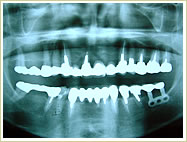

症例 56歳 女性 インプラント埋入数:6本 画像拡大

治療前 治療後